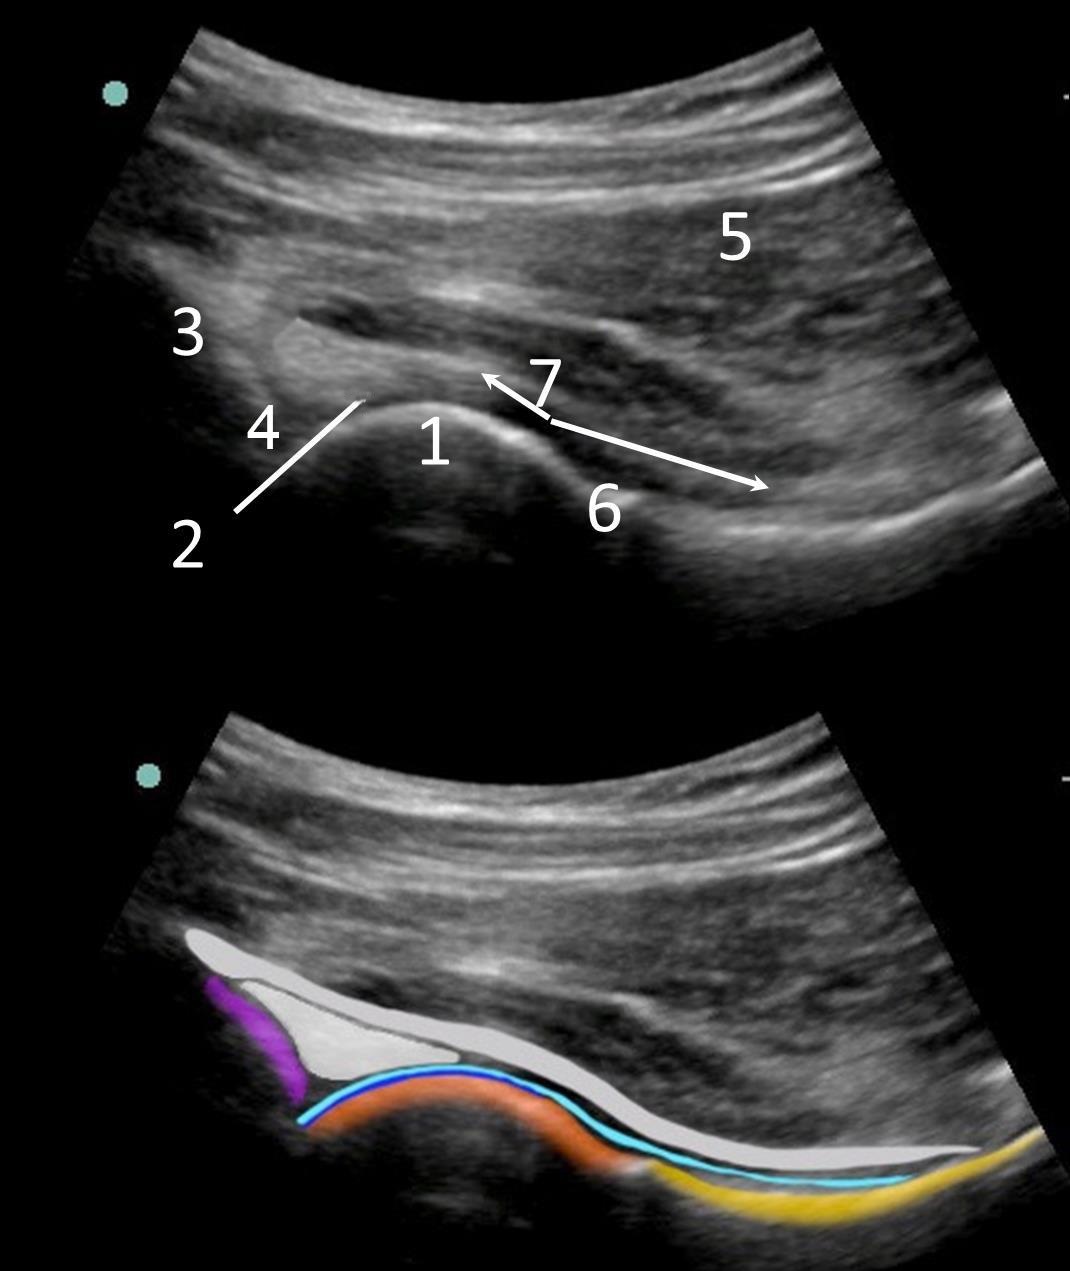

Bild: Vordere Hüfte 1

1. Hüftkopf

2. Gelenkknorpel (dunkelblaue Linie im Bild unten)

3. Acetabulum

4. Labrum

5. Darüberliegende Muskeln

6. Oberschenkelhals

7. Gelenkkapsel